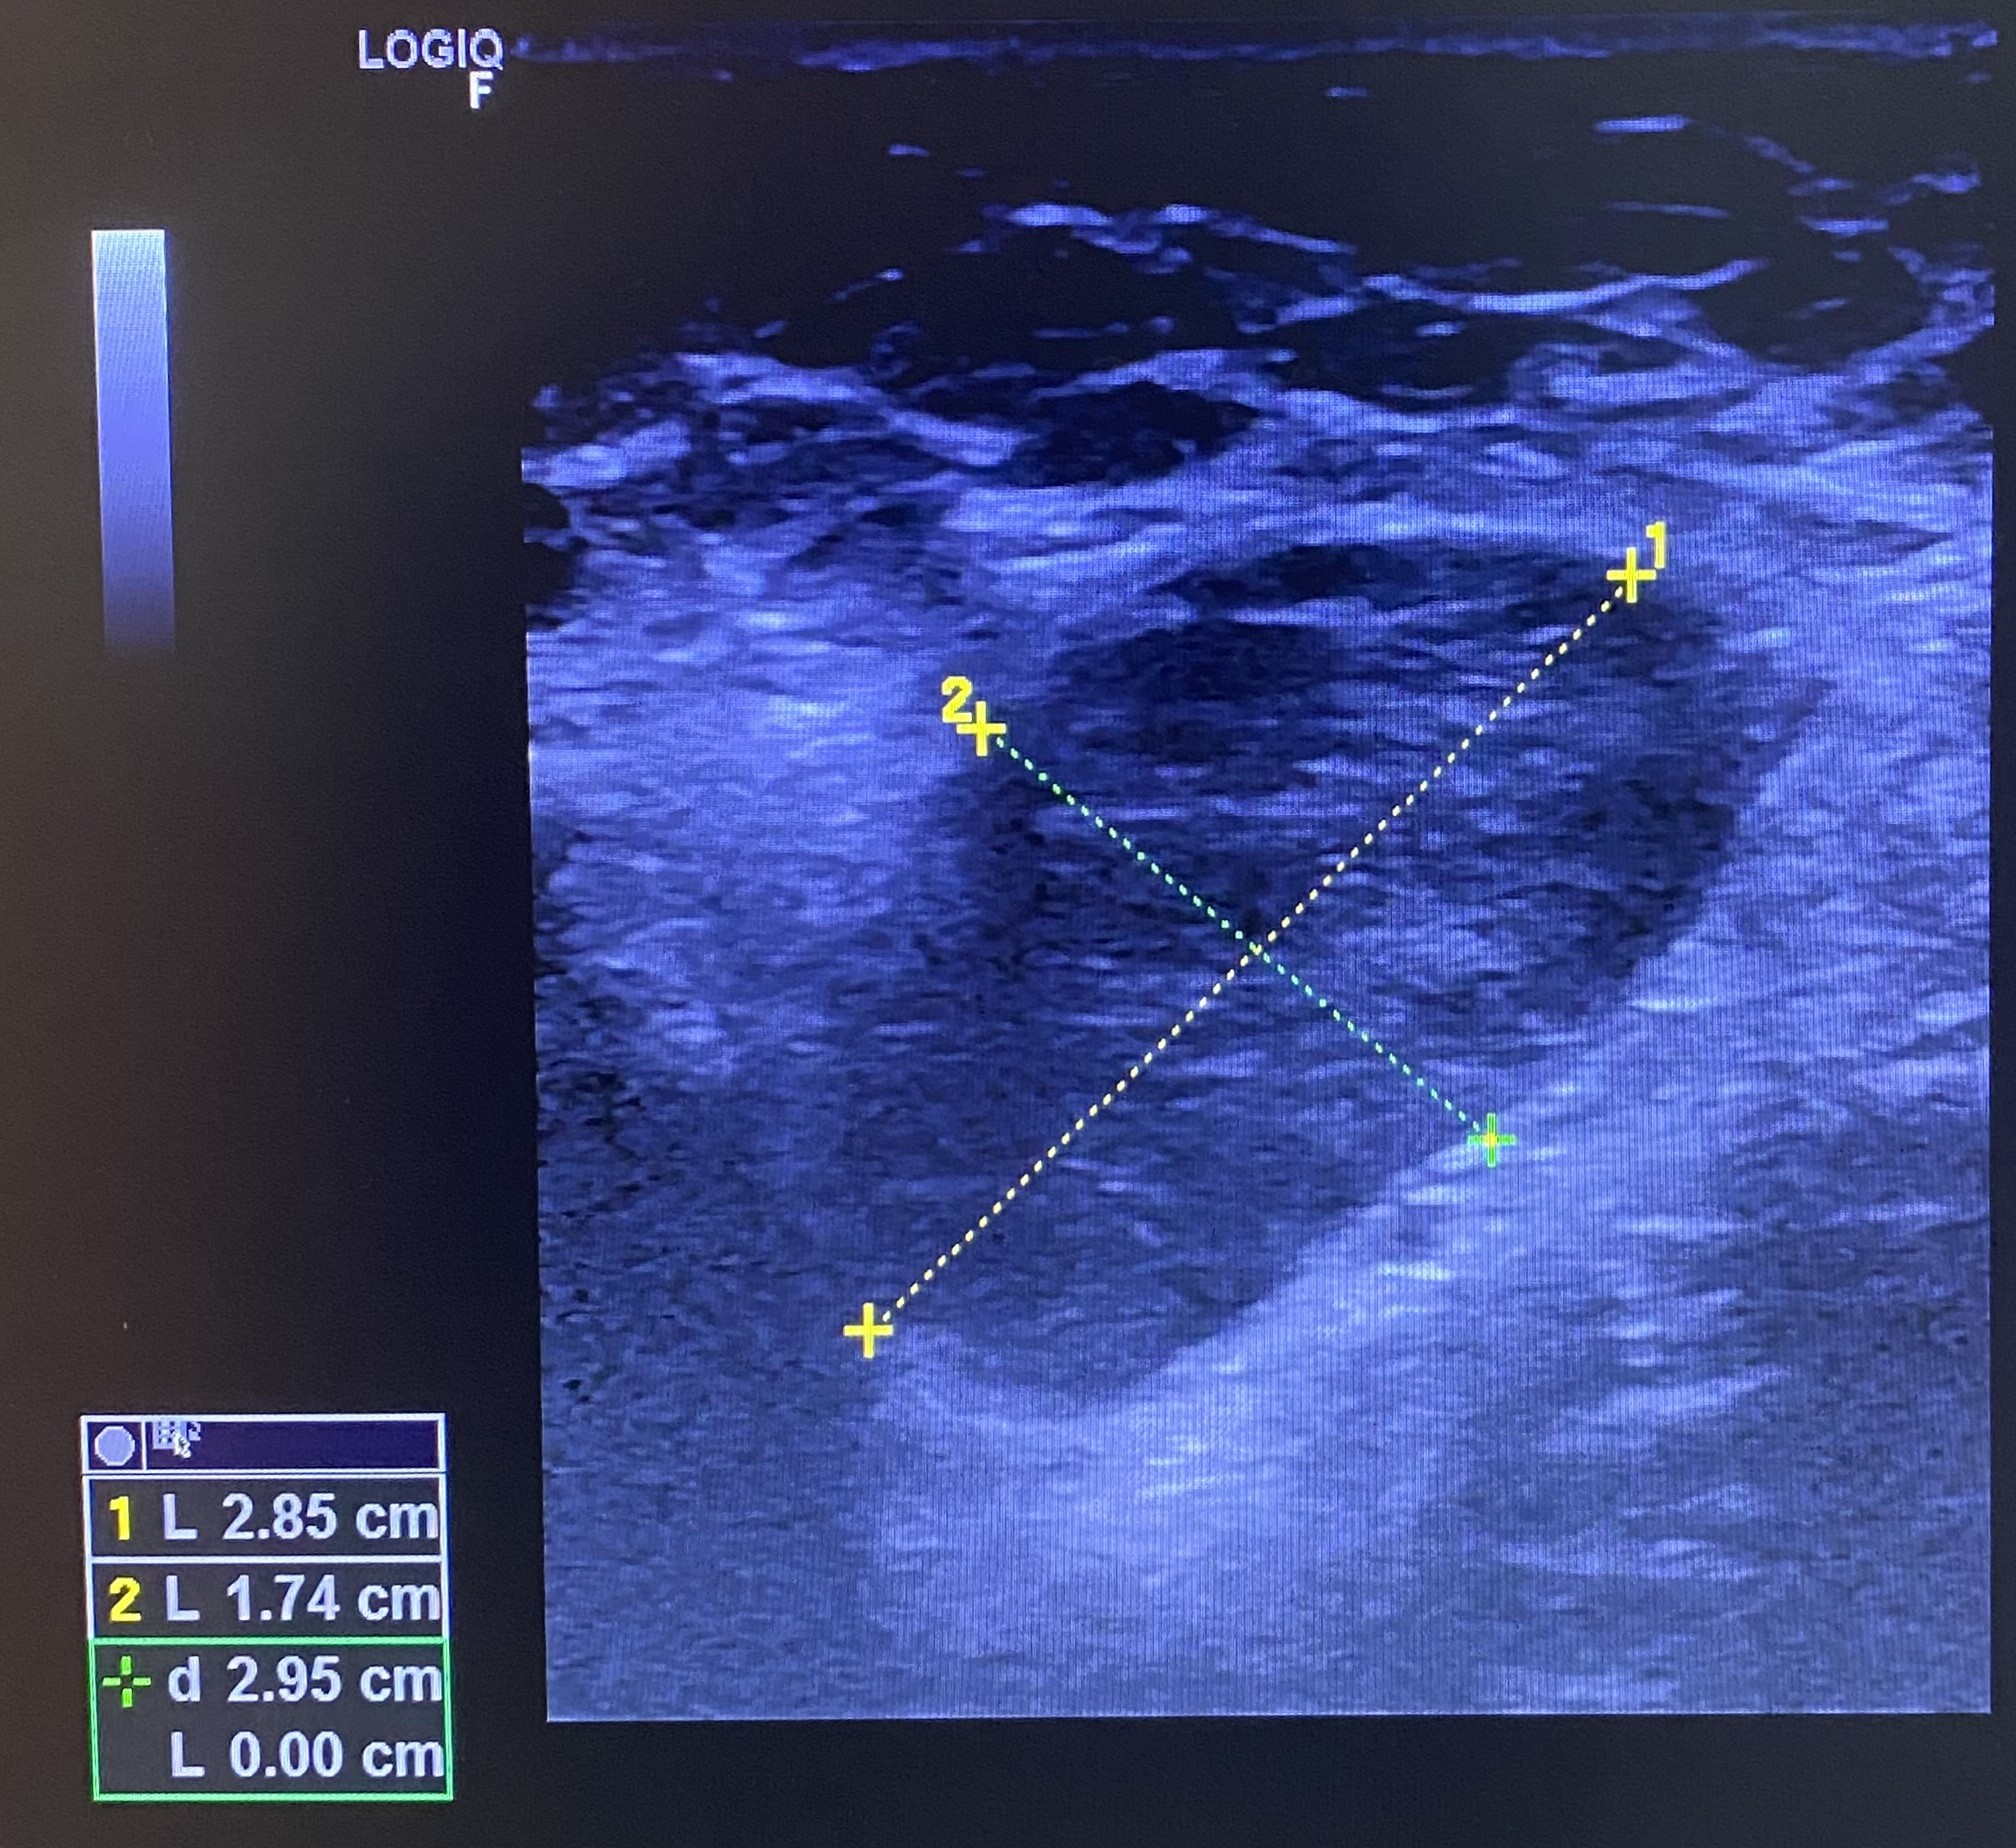

Se realiza una ecografía clínica en la consulta, objetivando múltiples adenopatías axilares izquierdas, la mayor con un tamaño de 2,85 x 1,74 cm. Se observa pérdida de hilio interior y aumento de diámetro transversal. El Doppler color es negativo.